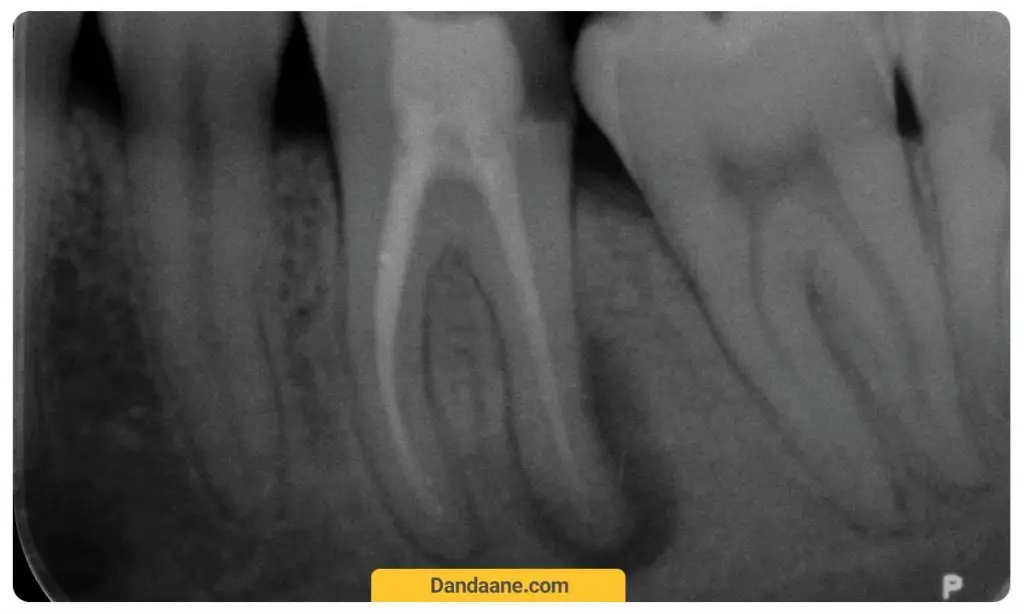

رادیوگرافی پری اپیکال یا (Periapical)

عکس دندان پری اپیکال یا عکس تک دندان معمولا برای نشان دادن وضعیت یک یا نهایتان دو دندان مجاور آن است. این تصویر بردداری تقریبا مشابه با عکس بایت وینگ است ولی تفاوتش با بایت وینگ در این است که ارتفاع کامل دندان از ریشه تا تاج به طور کامل در عکس قابل مشاهده است. از این عکس بیشتر برای بررسی وضعیت یک دندان خاص قبل از پر کردن دندان و یا کشیدن آن استفاده می شود.

قیمت و هزینه عکس دندان پری اپیکال یا تک دندان معمولا کمتر از قیمت عکس opg و برابر با 60 هزارتومان است.